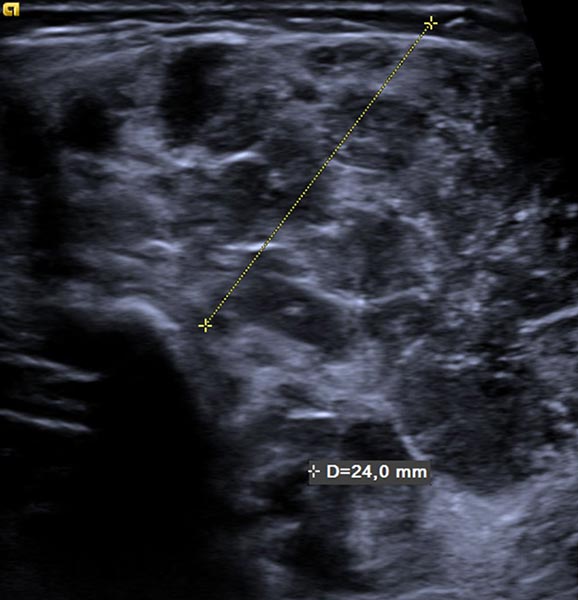

Starting from the 2nd week of life, the infant developed a total of 8 small typical, slow-growing cutaneous infantile hemangiomas. In addition, there was a circumscribed swelling ventrally in the middle of the left upper arm that was slowly increasing in size. The overlying skin was not discolored. The B-scan ultrasound shown here, at the end of the 4th month of life, reveals a relatively hypoechoic tumor in the subcutaneous tissue.

Power Doppler imaging shows strong perfusion of the mass, so that a vascular tumor is assumed. The strong blood flow is shown here in orange in the B-scan, while the direction of flow is not color-coded.